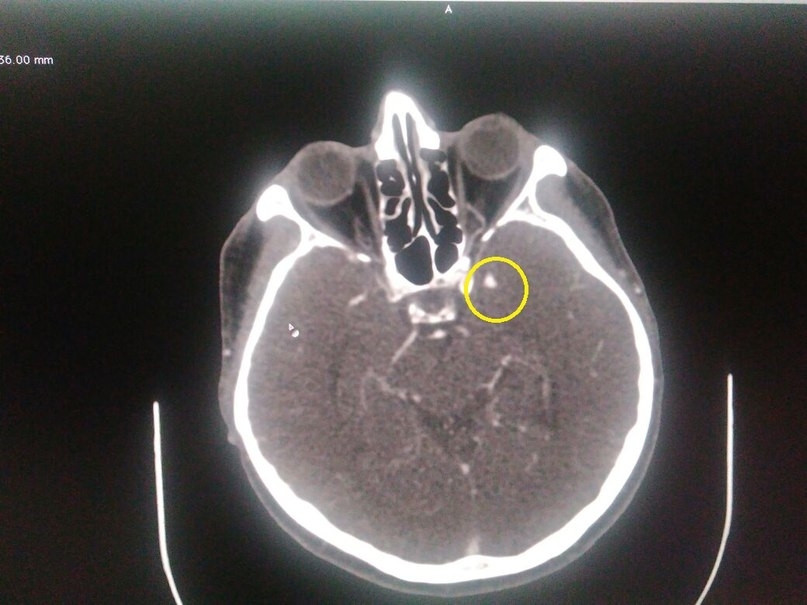

Бывают случаи, когда пациент жалуется на головную боль, частичную потерю или затуманенность зрения, онемение, боль в глазах. Невролог подозревает патологию сосудов головного мозга и направляет человека на МСКТ. Уже на исследовании выясняется, что причиной состояния была аневризма – образование на кровеносном сосуде, которое быстро растет и наполняется кровью. На снимках аневризма выделена кругом. Разрыв ее может привести к кровоизлиянию в головном мозге – это опасное для жизни состояние. При разрыве человек ощущает самую сильную боль, и нуждается в помощи врача.